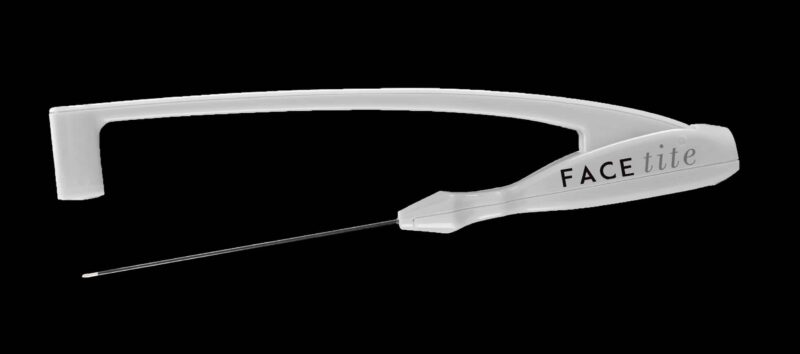

FaceTite es un tratamiento de vanguardia que permite moldear el rostro devolviendo un aspecto rejuvenecido y [...]

FaceTite es un tratamiento de vanguardia que permite moldear el rostro devolviendo un aspecto rejuvenecido y [...]